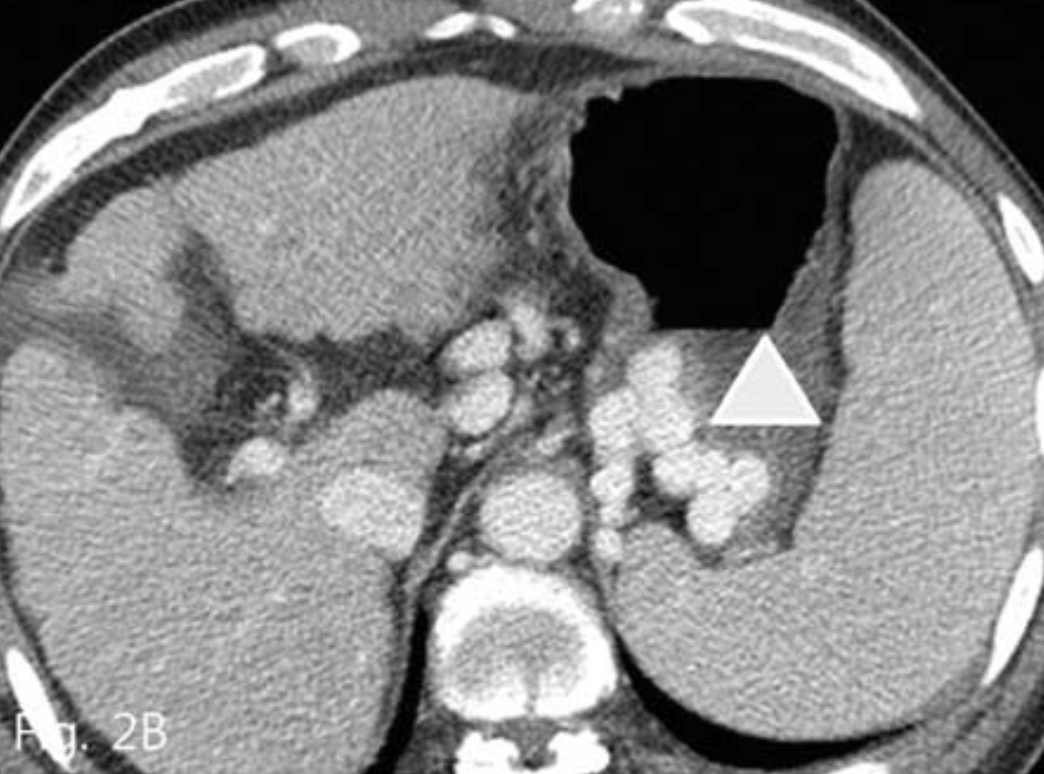

16mm vascular plug II(Amplatzer Vascular plug; AGA Medical, Golden Valley, Minn)를 삽입하였다. 그 후 wire를 따라 5-Fr catheter를 vascular plug를 지나 위치시키고 정맥조영술을 시행하였으며 주 유출정맥인 위대정맥단락은 막혔으나 대신 심장막정맥을 통한 곁가지 정맥배출이 좀 더 명확해졌다(Fig. 3B), 그래서 4개의 microcoil(Vortex; Boston Scientific, Cork, Ireland)로 이를 색전하였다(Fig. 3C). 그 후 5-Fr catheter를 통해 gelatin sponges(Gelfoam:

Fig. 3

B. Vascular plug placement (arrow) is performed in gastrocaval shunt Left inferior phrenic vein and pericardial vein (arrowhead) is more prominently visualized.

C. Left inferior phrenic vein is embolized with microcoil (arrow). And then gastric varices is completely filled with gelfoam mixture.